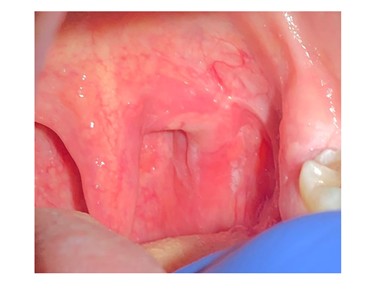

Vous l’examinez en consultation avec son scanner cervico-facial injecté et une IRM de l’oropharynx injectée réalisés en amont de la consultation mettant en évidence une asymétrie du voile du palais à prédominance gauche avec rehaussement modéré (fig.2) et une adénopathie parapharyngée homolatérale.

Fig.2 : IRM oropharyngée avec injection de gadolinium montrant une adénopathie parapharyngée gauche. Sur d’autres coupes a été observée une asymétrie du voile du palais à prédominance gauche